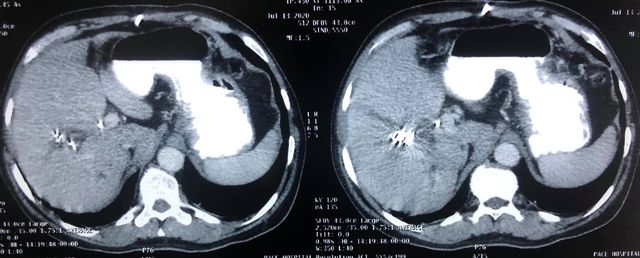

65 years of man type 3A hilar cholangiocarcinoma (complex hepatobiliary malignancy) with deep jaundice

SIX STEPS TO SUCCESS IN A ROLLER COASTER COVID CHALLENGE

- STEP 1: Left PTBD (to bring down jaundice)

- STEP 2: portal vein embolisation to allow growth of the small remnant left liver

- STEP 3: Right sided anterior and posterior PTBD to control persistent fever after initial intervention.

- STEP 4: admitted for surgery COVID positive CT CO-RADs 5 managed medically

- STEP 5: after 3 weeks waiting and repeat COVID PCR negative (couldn’t wait longer for risk of catheter dislodgement while waiting) underwent an Extended Rt hepatectomy with caudate lobectomy bile duct excision Left hepaticojejunostomy

- STEP 6: despite all the trials& tribulations and 7 hr surgery patient had a smooth recovery discharged by D6. An extremely satisfying result in a very difficult malignancy and a super motivated patient.